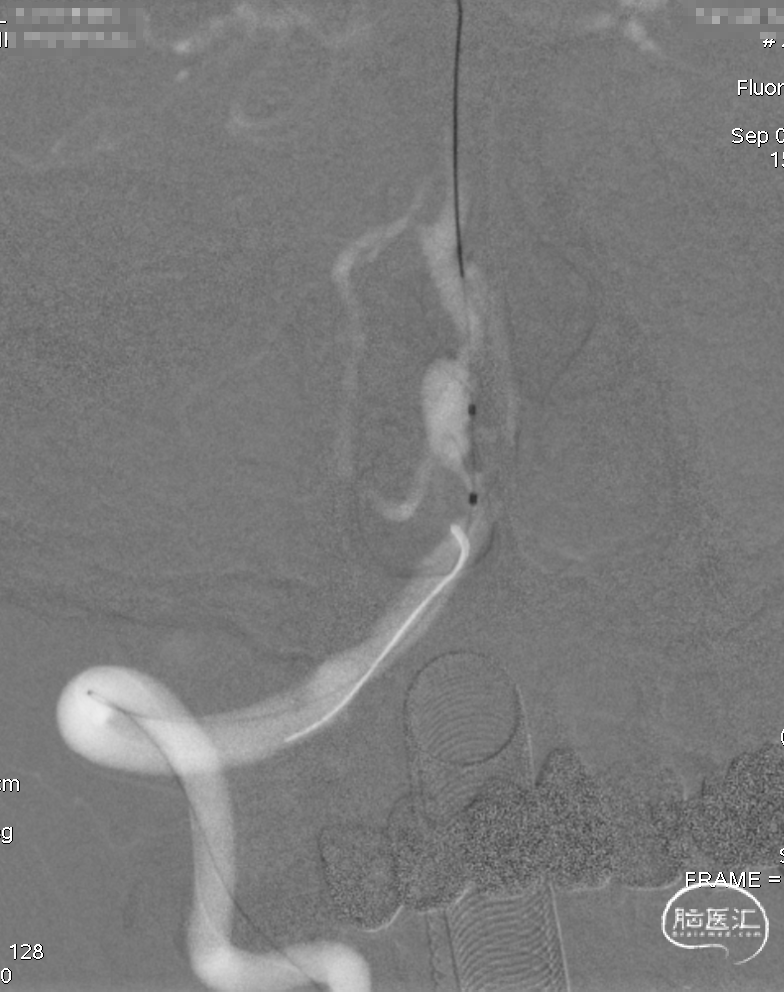

Marksman到位。

逐步释放Pipeline(3.00*30)。

支架完全释放,微导丝“按摩”支架。